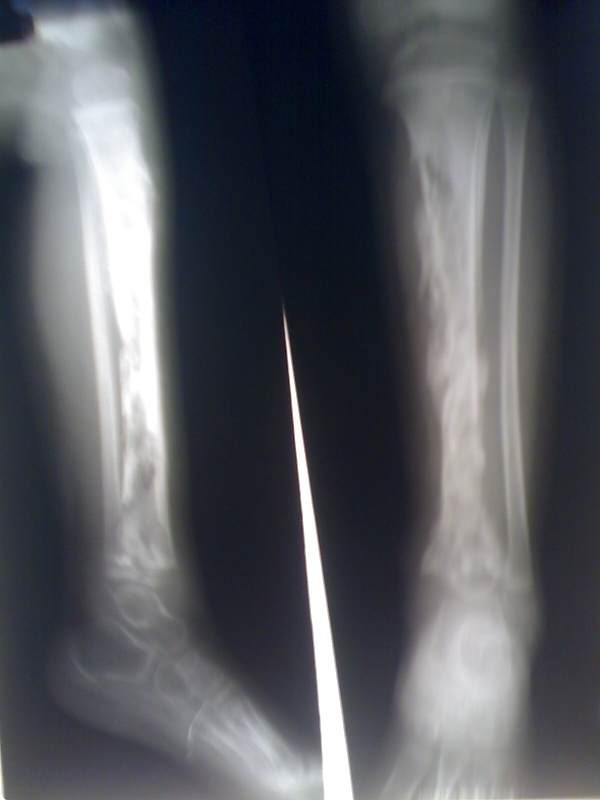

Как только костная ткань поражается микроорганизмами, к очагу заражения мигрируют лейкоциты, они выделяют литические ферменты, которые разлагают кость[4]. Распространение гноя по кровеносным сосудам приводит к секвестрации кости, таким образом формируется база для хронической инфекции. В это время организм пытается создать новую кость вокруг области некроза. Получающуюся новую кость часто называют покровом. При гистологическом исследовании эти особенности позволяют понять: острый остеомиелит или хронический.

Остеомиелит — инфекционный процесс, который охватывает всю кость, включая костный мозг. Когда этот процесс является хроническим, это может привести к костному склерозу и деформациям.